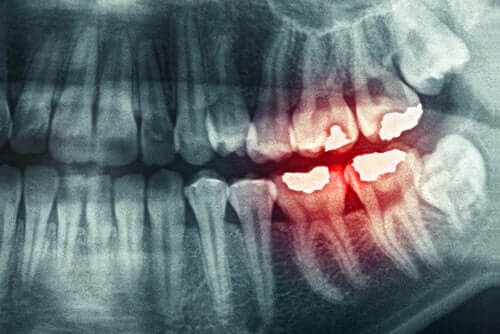

1. Tandgnissling kan orsaka morgonhuvudvärk

Tandgnissling är ett problem som drabbar fler människor än du kanske tror. Det innebär att du klämmer eller gnider tänderna medan du är vaken eller när du sover. I de mest extrema fallen krävs ett tandskydd.

Utan det kan det sluta med att du verkligen skadar dina tänder.

Spänningen som uppstår när du spänner käken kommer att leda till att huvudet värker på morgonen. Detta är vanligtvis resultatet av stress, oro, ångest eller depression. Ibland kan inte ens användningen av ett tandskydd förebygga huvudvärk.

Det bästa i dessa fall är att inte bara prata med en tandläkare – som kan ge dig ett tandskydd – utan även med en psykolog. Det är viktigt att lokalisera spänningen som du känner under natten när du gnisslar tänder.